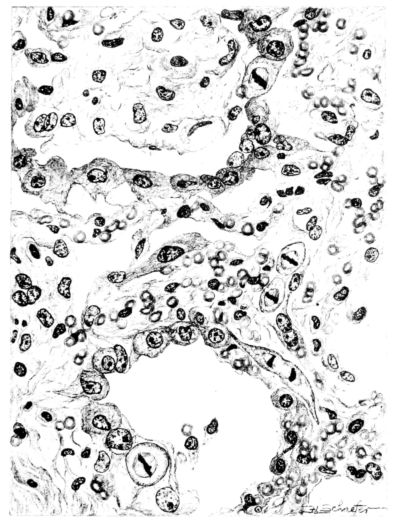

FIG. XI. AUTOPSY NO. 140. ILLUSTRATES A LATE CHANGE IN THE BRONCHIOLE; THE EXUDATE IS BEING ORGANIZED AND THE EPITHELIAL LINING IS PROLIFERATING AND HAS INVADED THE SURROUNDING LUNG TISSUE. COMPARE FIGURES XLVIII AND XLIX.

Microscopic examination of sections from the lung showed an extensive bronchopneumonia. The alveoli of an occasional group of lobules were filled with serum or red blood cells, while still other areas showed foci of necrotizing pneumonia, actual miliary abscesses in which there were large clumps of bacteria (Fig. XLI). Throughout the sections, however, the striking change was an organization of the exudate, which varied from a few fibroblasts to a well defined connective tissue almost obliterating the normal architecture (Figs. XLI and XLIV). The alveolar walls in some 28areas showed edema only, in others they were almost replaced by a thin line of fibrous tissue, and in still others, by a hyperplasia of the epithelium which almost filled their lumina. The bronchi exhibited similar changes, their lumina were filled with an exudate of desquamated epithelium and leucocytes, which in some places was organizing (Fig. XI), and there was a regeneration of epithelium evidenced by a piling up of the cells and the presence of mitotic figures in them. The interstitial tissue showed some edema. The tracheal epithelium was intact, but a few leucocytes and lymphocytes were scattered through the submucosa.

Microscopic examination of the lung showed the alveoli filled with an acute inflammatory exudate in many stages of degeneration and hyalinization (Fig. XLII). Abscesses were frequent, but were for the most part small. A similar necrotic mass was contained in the bronchi. There were, however, features of the microscopic picture that outweighed those already described. The alveolar and bronchiolar exudates were everywhere being invaded by a young granulation tissue, rich in fibroblasts and capillaries. Mononuclear cells abounded in the new tissue. Even more striking than the mesodermal new growth was the epithelial proliferation which could be seen in many areas. It not only attempted to cover the denuded bronchial surfaces, but stretched over masses of exudate and granulation in the lumina and extended in tongue-like projections for a considerable distance into the surrounding lung tissue (Fig. XLVIII).